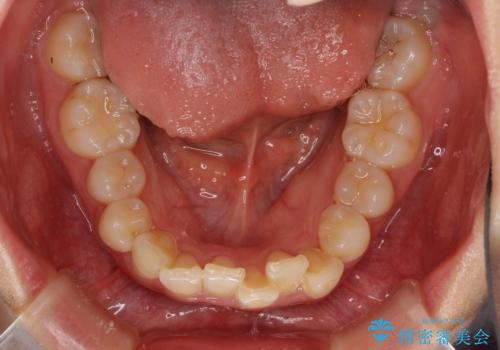

- デコボコの歯列が気になるとことで来院された患者様です。

歯列不正としては軽度であったため、インビザラインでもワイヤー装置でも対応可能でしたが、ご本人の希望によりインビザラインによる矯正治療を行うこととしました。

マウスピース矯正は、自己管理が非常に重要と事前にお伝えしておりましたが、毎日のマウスピース装着が遵守できず、ワイヤー装置での矯正治療へ変更することとなりました。